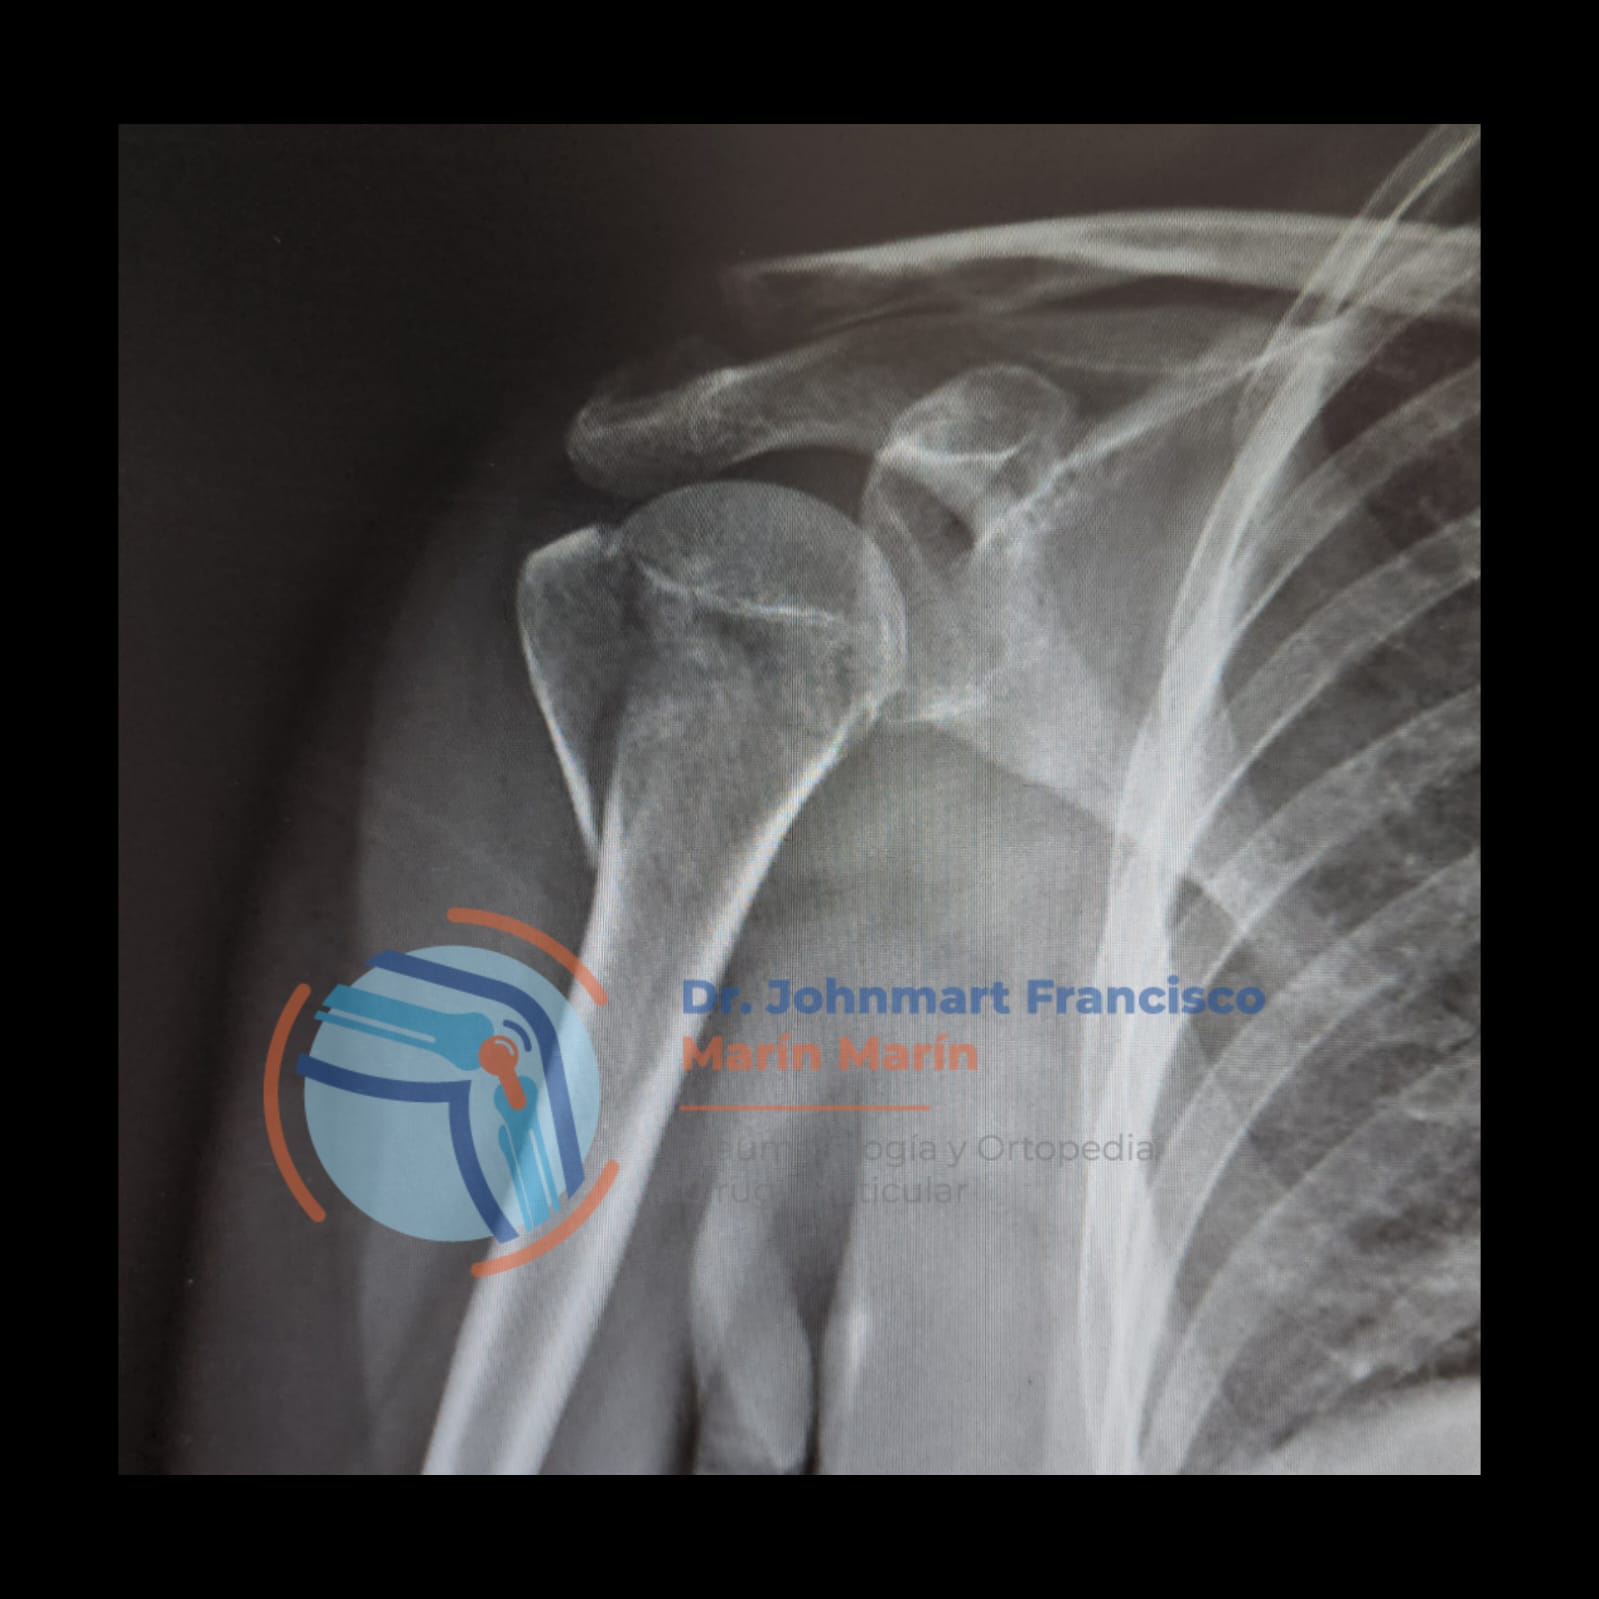

ARTROSCOPIA

Procedimiento quirúrgico, el cual se realiza principalmente en hombro, muñeca, cadera, rodilla, tobillo.